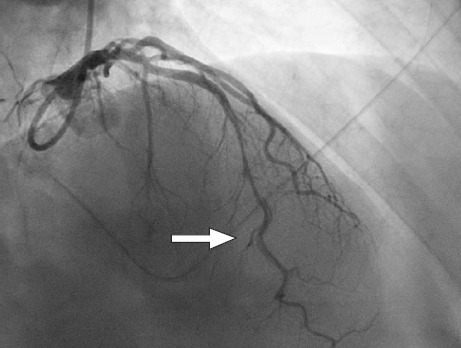

A male patient presented with cardiac arrest attributed to anterior ST-segment elevation myocardial infarction from type 1 spontaneous coronary artery dissection. Subsequent imaging confirmed fibromuscular dysplasia in noncoronary arterial segments. The patient was started on guideline-directed medical therapy and referred to cardiac rehabilitation, showing substantial improvements in clinical status. With greater awareness and advancements in imaging, spontaneous coronary artery dissection has been more frequently recognized, and although as many as 81% to 92% of all cases occur in female patients, it can be seen among men, as well. Adjunctive imaging for arteriopathies may help establish the diagnosis for equivocal causes of acute coronary syndrome in women and men.

Abstract Image